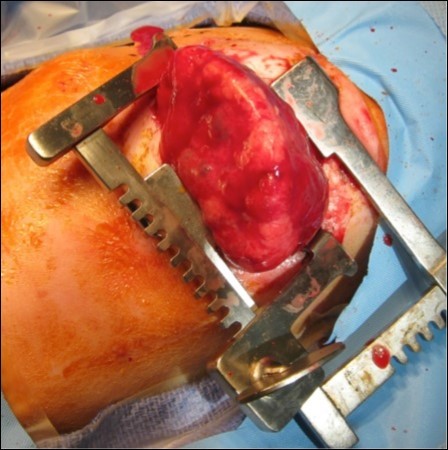

A 33-year-old gravida 1 initially presented for a detailed ultrasound in our office with fulminant fetal hydrops and a noted mass in the left chest. Initial evaluation included maternal viral studies (negative parvovirus, CMV, toxoplasmosis), maternal karyotype (46XX), and amniocentesis (46XX, microduplication in the 16p11.2 region). Given concern for CPAM and hydrops at 20 weeks and 3 days, the patient was referred to a fetal therapy center. Ultrasound at the fetal therapy center showed an estimated fetal weight of 824 grams (>97th percentile) and fetal hydrops (scalp edema of 8mm, skin edema of 4mm, and ascites of 14mm). The diaphragm was intact and the maximal vertical pocket was 6.8 cm. The left chest mass measured 6.6 x 5.3 x 4.4 cm and was multiloculated with microcystic and macrocystic lesions (type 1); the dominant cyst measured 4.0 x 3.2 cm, Figure 1. Secondary to mass effect, the heart was severely displaced into the right chest with a CVR of 3.9cm2. There was no noticeable peristalsis of the cystic structures and no systemic identifiable arterial blood supply. Fetal echocardiogram showed a structurally normal heart significantly shifted in the right chest. After extensive counseling, the patient opted for administration of antenatal corticosteroids and thoraco-amniotic shunt placement. The patient received betamethasone 12mg intramuscularly prior to shunt placement at 21 weeks and 4 days and 21weeks 5 days. Two double pigtail Harrison thoraco-amniotic shunts were placed by inserting a 13 Ga cannular-trocar into the maternal abdomen and uterus (the first shunt into the largest cyst (left, anterior, inferior) and the second into an additional dominant cyst (anterior, central portion of the mass). Both cysts drained completely after insertion. Epidural anesthesia with IV sedation were used as well as tocolytics as needed during the procedure. The post-procedure CVR was 1.3cm2 with decreased mass effect on the heart. Post-operative plan consisted of genetic consultation, fetal MRI, and serial monitoring of the CVR.

Figure 1.CPAM noted at initial fetal surgery consultation; sagittal view on the left and transverse view on the right